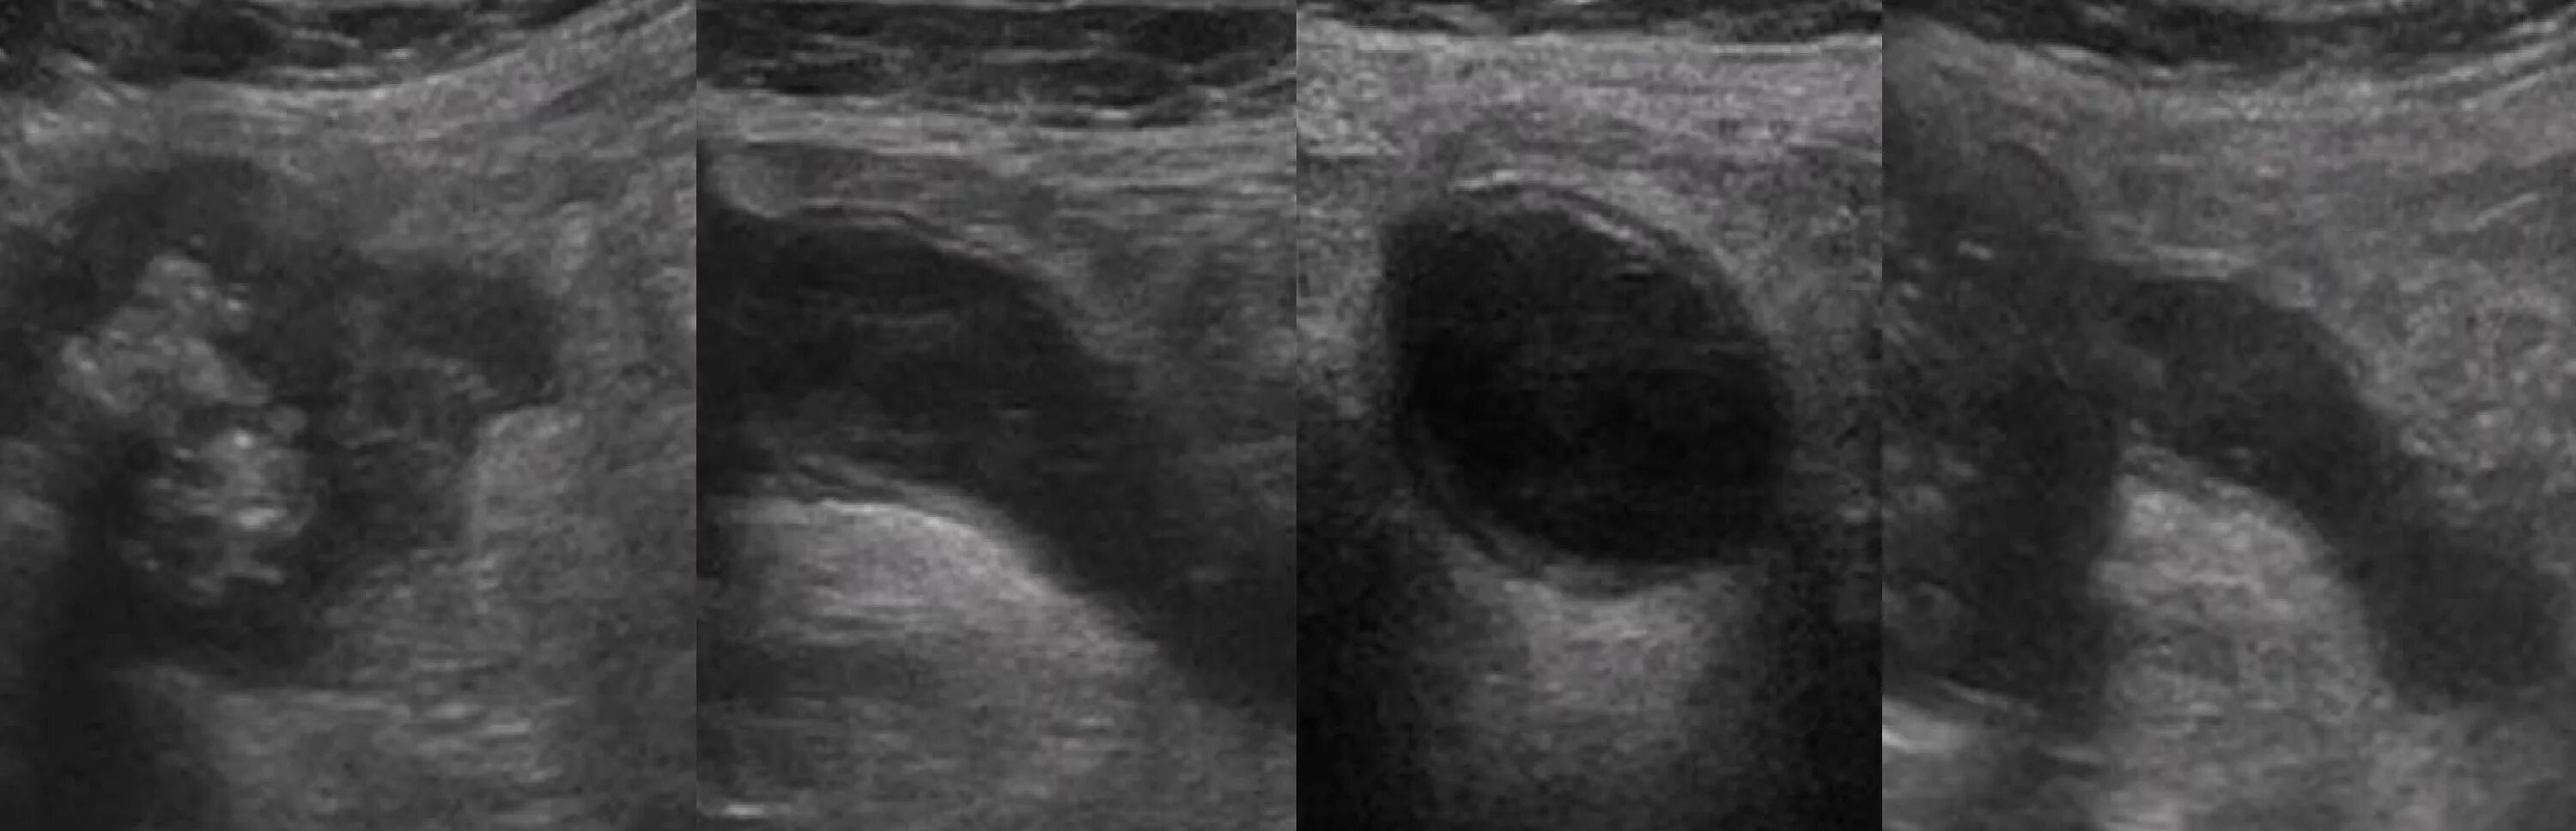

Аппендицит на узи можно ли